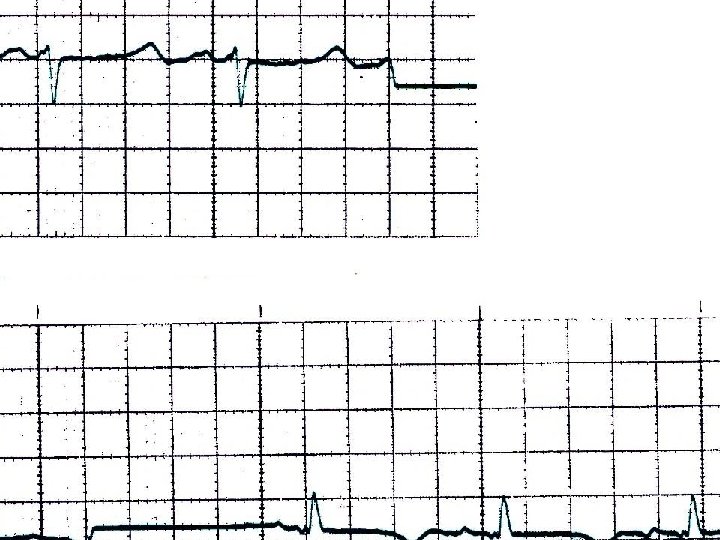

Clinical manifestations of hypocalcemia Prolonged QT interval due to hypocalcemia

• W. B. C 7. 910 / u. L. , Neu 76 %, Lymph. . 8 %, Mono 15 %, Ht 32. 1 %, M. C. V. 74. 6 f. L, M. C. H. 22. 9 pg, P. L. T. 378. 000 /u. L, Σάκχαρο 117 mg/dl, Ουρία 65 mg/dl, Κρεατινίνη 2. 1 mg/dl, Αμυλάση 141. U/L, Ολ. Χολερυθρίνη 0. 3 mg/dl, Χοληστερίνη 104 mg/dl, Τριγλυκερίδια 68 mg/dl, Ολ. Λευκώματα 6. 4 g/d. L, Αλβουμίνη 5. 0 g/d. L, Ουρικό οξύ 8. 9 mg/d. L , SGOT 63 U/L, SGPT 58 U/L, ALP 69 U/L, γGT 36 U/L, LDH 521 U/L, Na 139 mmol/L, K 3. 0 mmol/L, Ca 3, 9 mg /dl • Αέρια αίματος : p. H 7. 36, p. CO 2 23 mm Hg, p. O 2 120 mm Hg ( με μάσκα Venturi ), HCO 3 13 mmol / L, Lact 10. 7 mmol / L, • SO 2 : 99 %, Σάκχαρο 243 mg / dl